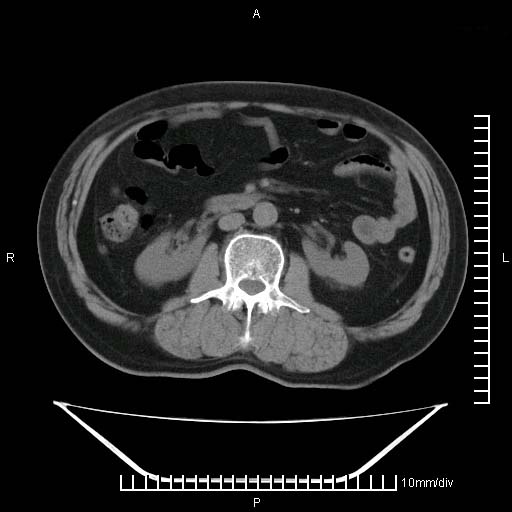

标题: CT25082:肝脏增强:男性,70岁 [打印本页]

标题: CT25082:肝脏增强:男性,70岁

患者以心脏疾病收住院,腹部无明显症状,b超查肝脏有占位。

增强效果不理想。考虑转移,胆囊壁明显增厚,不排除胆囊癌肝转移。

牛眼征,中心坏死无强化,外缘强化,最外缘又见低密度,考虑转移,与脓肿鉴别

肝内多发转移瘤,右下肺炎症并少量胸水。胃壁增厚建议胃镜,胰尾部“病变”为肠管。

1)肝脏多发性转移瘤(不排除胰尾癌转移所致可能)。2)腹水。3)右侧少量胸腔积液。

ct25082 结果:转移瘤

外院mr结果:胰尾恶性占位。